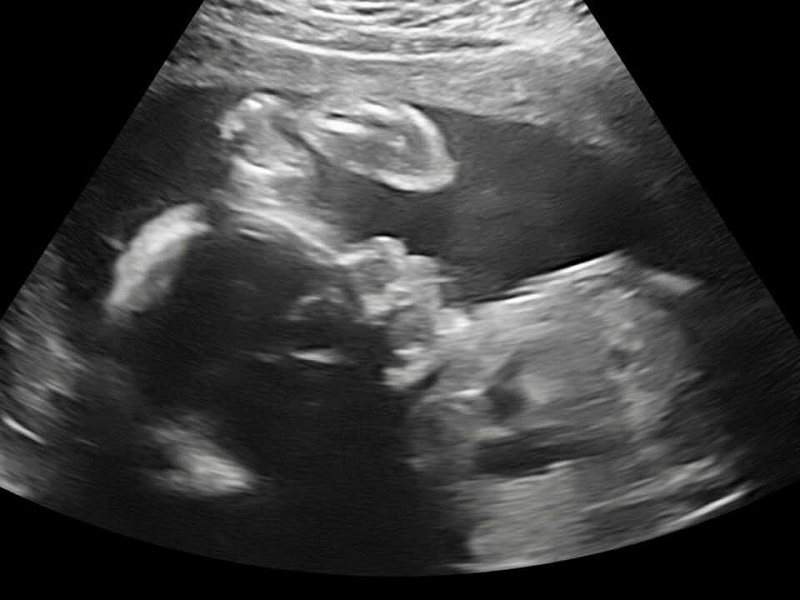

At Heather's 20-week ultrasound, the baby hid behind her ribs. The OB-GYN couldn't see the entire heart. No worries; they scheduled another exam in two weeks.

Working the wand around Heather's belly, the chatty technician turned quiet. The OB-GYN arrived with a look that confirmed something was wrong.

The appointment began with a fetal echocardiogram. The doctor watched from another room, the images confirming the depth of the problems.